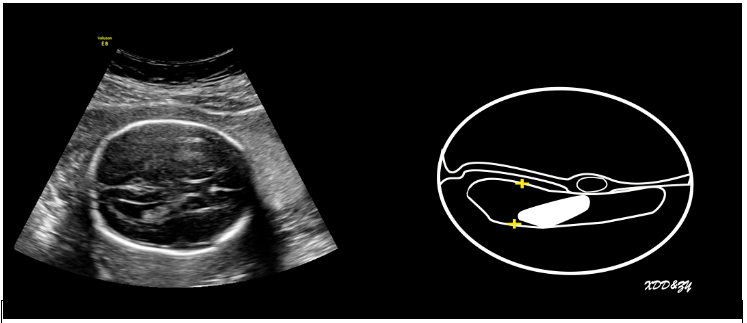

侧脑室测量(图1),测量原则:①测量侧脑室三角区,该区域16~40周恒定;脑室压力增高时该位置最敏感。②“量远不量近,量内不量外”,测量远场,避免近场伪像,测量内径而非外径。

图1